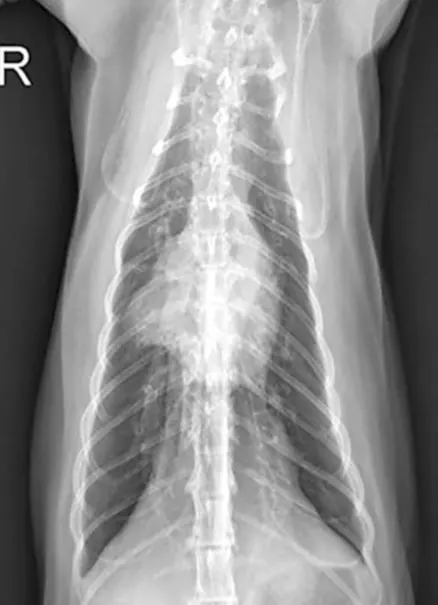

Figure 2

Thoracic radiograph of a cat with asthma showing a diffuse bronchial pattern and collapse of the right middle lung lobe. Figure courtesy of Oklahoma State University Center for Veterinary Health Sciences

• Classic thoracic radiographic findings in patients with feline asthma include a diffuse bronchial or bronchointerstitial pattern, hyperinflation, and/or collapse of the right middle lung lobe caused by mucus plug obstruction.3,4 (See Figure 2.) Up to 23% of asthmatic cats have normal thoracic radiographs.5